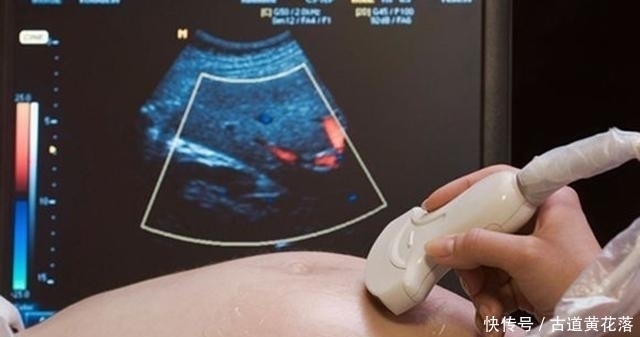

一个是四维排畸筛查,主要通过B超检查看胎儿是否存在畸形。